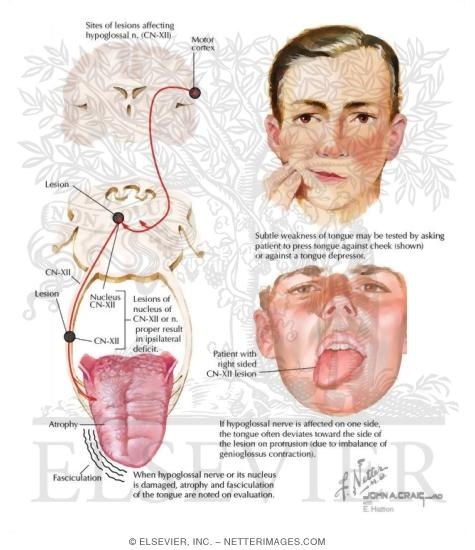

Neuroanatomy, Cranial Nerve 12 (Hypoglossal) – StatPearls – NCBI Bookshelf

Hypoglossal Nerve Neuropathy and Dysarthria | Radiology Key

Persistent Idiopathic Isolated Hypoglossal Nerve Palsy – Practical …

Hypoglossal Nerve Palsy Treatment – Captions HD